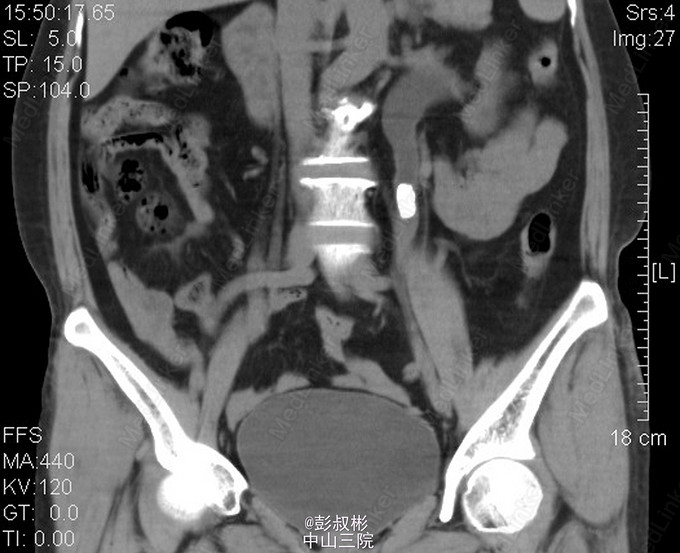

女性,56岁,左腰酸胀不适2年余。KUB:左输尿管上段结石,大小约16mm×10mm。腹部CT:左输尿管上段结石,并左肾、输尿管重度梗阻性积水。核素双肾动静态显像:左肾功能中重度减退,右肾功能正常。